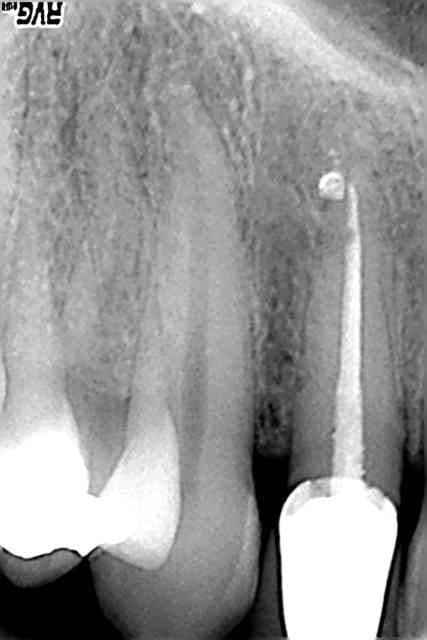

tiens, pour obtenir ce genre d'image, y a pas besoin de gutta tueuse de microbe. conclusion faut plus se préoccuper de la préparation que de l'obturation.